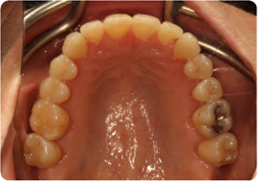

Each case shows the front view and an arch or side view, before and after BioLign Method-guided treatment.

All cases treated within 6–12 months.

Crowding with irregular gaps resolved into even alignment